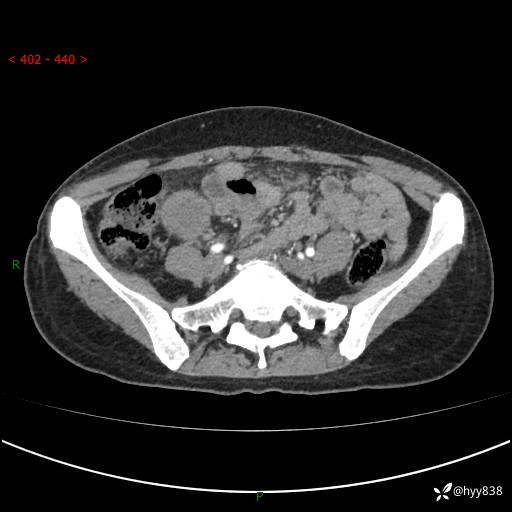

年轻女性,发现腹腔肿物1周。圆圆的肿物,诊断有难度---结果公布~

现病史:患者自诉于1周前无明显诱因出现剑突下间断性隐痛,尚可忍受,不向其它部位放射,无恶心呕吐、腹泻便秘等不适,于当地市第二人民医院就诊,行CT结果示:1.右中腹占位,间叶组织来源可能2.小肠梗阻3.盆腔积液4.腹腔积液5.副脾6.肝囊肿;于荆州二医行抗炎,抑酸,护胃,补液等对症支持治疗;患者病情好转,今为求进一步诊治,遂来我院门诊就诊,门诊以“腹腔肿瘤”收入院。 起病以来,患者精神、睡眠、饮食一般,大小便正常,近期体力体重无明显改变。

腹部CT增强(外院平扫)